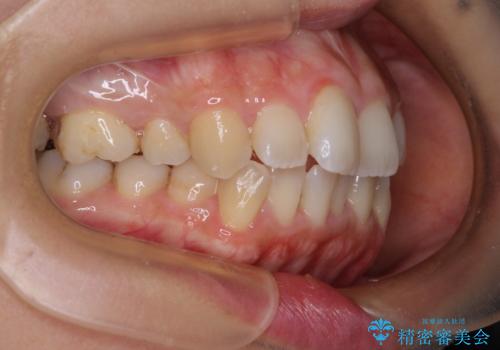

前歯のデコボコを改善 インビザラインの矯正治療

- 前歯のデコボコを治したいとのことで来院された患者様です。

上下顎ともに歯列全体の後方移動とIPR(歯と歯の間を削る)によってデコボコが解消するように設計し、インビザラインにより治療を行うこととしました。